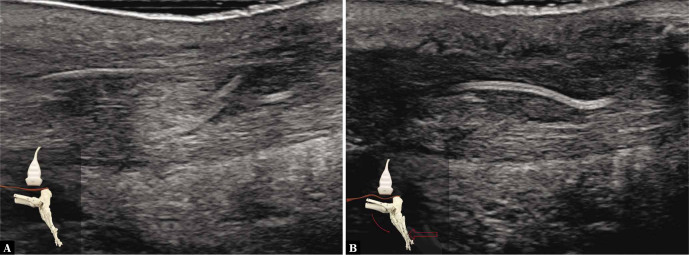

Por otro lado, podemos ver esta imagen de otro paciente también operado hace 3 meses por una rotura del tendón. Al igual que antes, a la izquierda el tendón se encuentra en reposo y a la derecha durante una flexión plantar activa contra resistencia.

A diferencia de lo esperado en un tendón funcional, durante la contracción las fibras aparecen onduladas y sin tensión, al igual que las suturas quirúrgicas visibles en la imagen. Esto indica que el movimiento no se realiza gracias al tríceps sural, sino probablemente por la acción compensatoria de otros flexores plantares. El tendón, en este caso, se comporta como una estructura elongada y funcionalmente ineficaz.